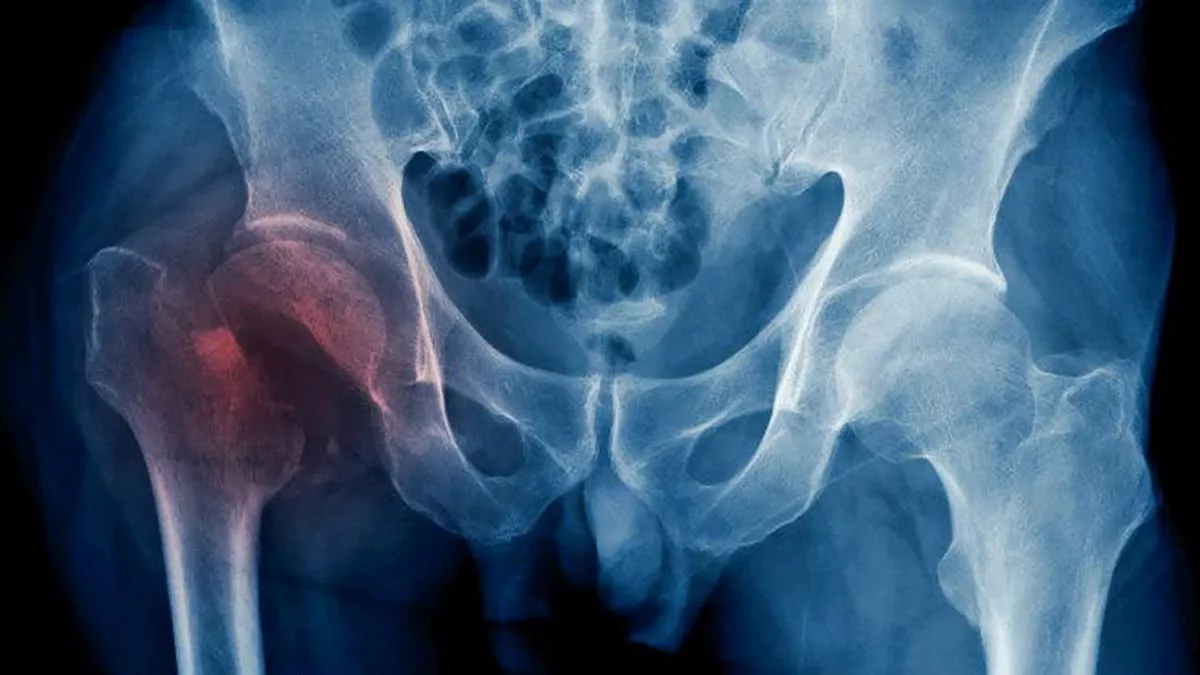

La cadera es una articulación formada por la unión del fémur (hueso del muslo) y el acetábulo (parte de la pelvis). Cuando decimos que un paciente sufre una fractura de cadera, en realidad, hacemos referencia a la extremidad proximal del fémur. Esta lesión es muy frecuente en las personas mayores, ya que tienen los huesos más frágiles por la osteoporosis y mayor riesgo de caídas por problemas de equilibrio o movilidad.

En cuanto a la técnica quirúrgica empleada para tratar la fractura de cadera, existen dos opciones principales: la fijación de la fractura (mediante distintos tipos de osteosíntesis- clavos, placas, tornillos-) y el reemplazo de la articulación por una prótesis. La elección de una u otra depende fundamentalmente, del tipo y la localización de la fractura , aunque cada caso es evaluado detalladamente por el profesional.

“De forma muy generalizada y refiriéndonos al tema en cuestión, podemos decir que la fijación de la fractura se suele realizar aquellas que afectan al macizo trocantérico (extracapsulares), mientras que optamos por una prótesis en aquellas que la zona afectada es el cuello femoral (intracapsulares). "En cualquier caso, el objetivo es lograr una estabilidad óptima que permita al paciente apoyar y caminar lo antes posible, salvo en casos individualizados”, explica el doctor Badillo.